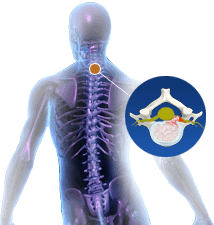

Cervical Herniated Disc

Herniation of a disc is an anomalous spine condition characterized by leakage of the inner contents